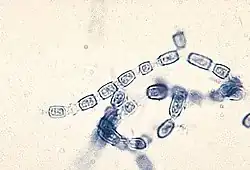

Coccidioides immitis

Coccidioides immitis is a pathogenic fungus that resides in the soil in certain parts of the southwestern United States, northern Mexico, and a few other areas in the Western Hemisphere.[2]